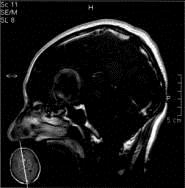

问题 病历摘要:??患者男性,56岁,因右侧视力下降伴视野缺损2个月来院就诊,诉头痛,无明显头晕,无视物重影,无恶心呕吐,无肢体抽搐,无肢体乏力,胃纳佳,大小便正常,既往史无特殊,入院检查:神志清楚,言语清楚,体毛分布正常,左侧视力4.6,右侧视力4.0,粗侧右颞侧视野缺损,左侧正常,颈软,四肢肌张力正常,肌力正常,病理征(-)。 大小为多少的动脉瘤称之为巨型动脉瘤?提示:该患者行全脑血管造影,诊断前交通巨型动脉瘤并部分血栓形成。